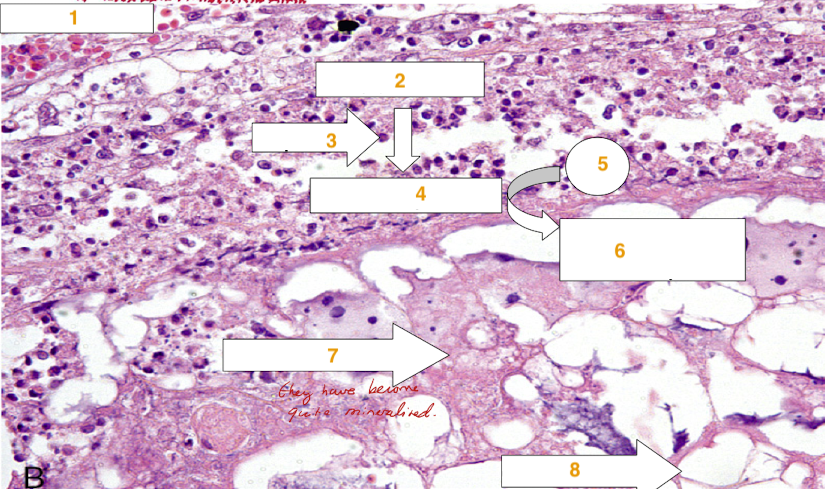

Name the following features on the slide of fat necrosis below: